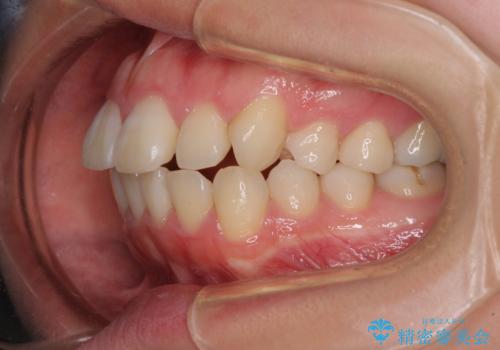

- 口元の突出感を気にして来院された患者様です。

口元を積極的に引っ込めるために、上下左右の第一小臼歯を4本抜歯することとし、ワイヤー装置による矯正治療を行うこととしました。

上下前歯がくちばしのように突出していましたが、抜歯矯正により口元が引っ込み、唇が閉じやすくなり、鼻の下の膨れた感じも解消されました。